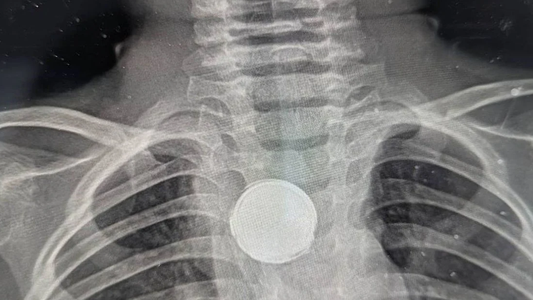

Este nuevo médico pidió una radiografía del tórax de Luke, algo que a priori suena un paso cotidiana para descartar afecciones.

"Le vi poner una mirada extraña", reveló Erica, a quien los médicos preguntaron si Luke se había tragado una moneda o si usaba un collar con un botón, a lo que ella respondió por la negativa.

Tras una hora en el quirófano, uno de los profesionales de la salud confirmó lo que suponía: habían hallado una batería de litio pegada al interior del esófago de Luke.

La sorpresa fue que la pila estaba envuelta en cinta aislante, y de acuerdo a lo que especulan los médicos esa pudo ser la razón que le salvó la vida al niño.

La batería había permanecido alojada en la garganta de Luke durante cinco semanas y había dañado el tejido esofágico, que los cirujanos intentarán reparar.